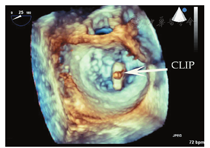

超声心动图在MR介入术中起着不可或缺的作用,下面以目前最为成熟的经导管二尖瓣夹合术MitralClip为例,阐述MR介入术中的超声评价。MitralClip是在TEE实时监测和引导下的操作,所有的导管操作由TEE监测和引导[16]。TEE首先引导房间隔穿刺,使得房间隔穿刺点距二尖瓣瓣环平面的高度3.5~4 cm(图11)。之后,TEE引导输送系统进入左心房并调弯、顶端垂直指向二尖瓣口。接着,TEE引导夹合器在二尖瓣上方定位,夹合器进入左心室,引导夹合器捕获和夹合瓣膜。夹合器捕获瓣膜位置,应该位于彩色多普勒显示反流束最大处。在整个手术过程中,两个超声切面非常重要,为手术的工作切面(X-plane双切面),包括三腔切面(左心室长轴切面)及二尖瓣交界处两腔切面(图12),前者可以显示二尖瓣A2、P2的位置,捕获瓣膜前二尖瓣夹合器应该在这个切面显示为"V"形,此时瓣夹合器臂与二尖瓣开放线垂直,分别位于A2、P2的位置,在该切面通过调整夹合器位置可使得夹合器更靠近前叶或后叶;后者显示P1,A2,P3,捕获瓣膜前二尖瓣夹合器在该平面应该为直线形,在该切面通过调整夹合器位置可使得夹合器更靠近内交界(3)或外交界(1)。另外一个工作切面为三维超声心动图的"二尖瓣外科视野",可以整体观察夹合器的位置、臂指向的方向(图13)。目前有限经验显示,经心尖二尖瓣夹合术(ValveClamp)术中超声指导和MitralClip总体上类似,但仍有部分差异,其超声规范尚在探索中。